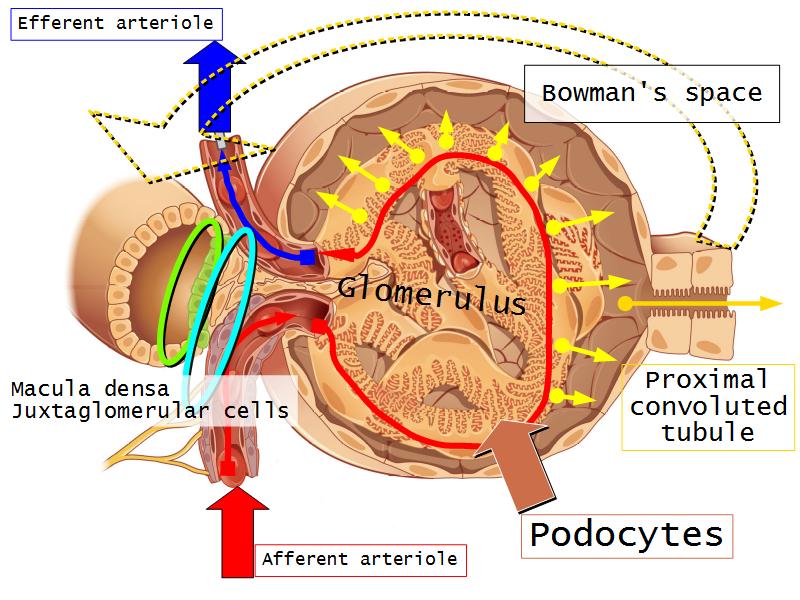

- Basic anatomy of the kidney

- Basic arrangement of nephrons and collecting tubules in the kidney

- Structure of the nephron and collecting tubules

- The renal corpuscle

- Make an annotated diagram of a nephron, including the juxtaglomerular apparatus. Indicate the flow of blood and water in each part, and how solutes are filtered, secreted and reabsorbed.